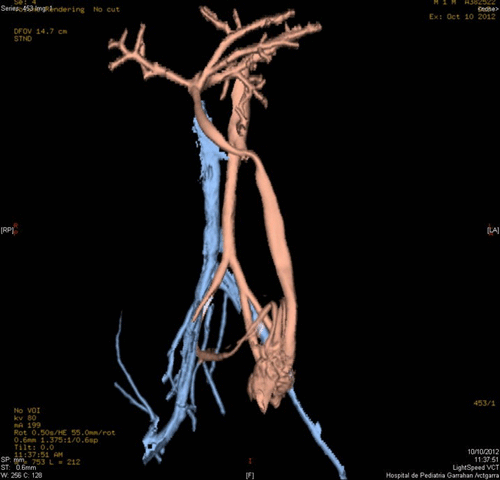

Figure 2: Dilated blood vessels showing turbulent bloodstreams.  |

A 20-day-old male neonate with an umbilical hernia was referred to our hospital because of persistent wet umbilicus. Umbilical examination showed a 2 cm diameter umbilical hernia and a long epithelialized pulsatile cord with granulomatous tissue at its end (Fig. 1). Palpable thrill was note at the midportion of the umbilical cord. Doppler ultrasonography revealed a mass at the end of the umbilical cord harboring dilated blood vessels with turbulent blood flow (Fig. 2). This vascular mass continued to the umbilical vein, which was dilated and flowed into the liver. Abdominal contrast-enhanced computed tomography revealed umbilical AVM; the umbilical arteries were patent from both internal iliac arteries, flowed into the mass directly at the end of the umbilical cord, and the dilated umbilical vein flowed out from the mass, continuing from the umbilicus to the umbilical part of the portal vein in the liver (Fig. 3, 4).